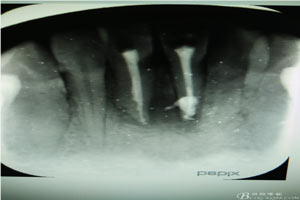

圖2.術(shù)前的根尖片影像、31根管治療已做,欠填少許。31、41根尖有橢圓形陰影,未見(jiàn)明顯骨白線。